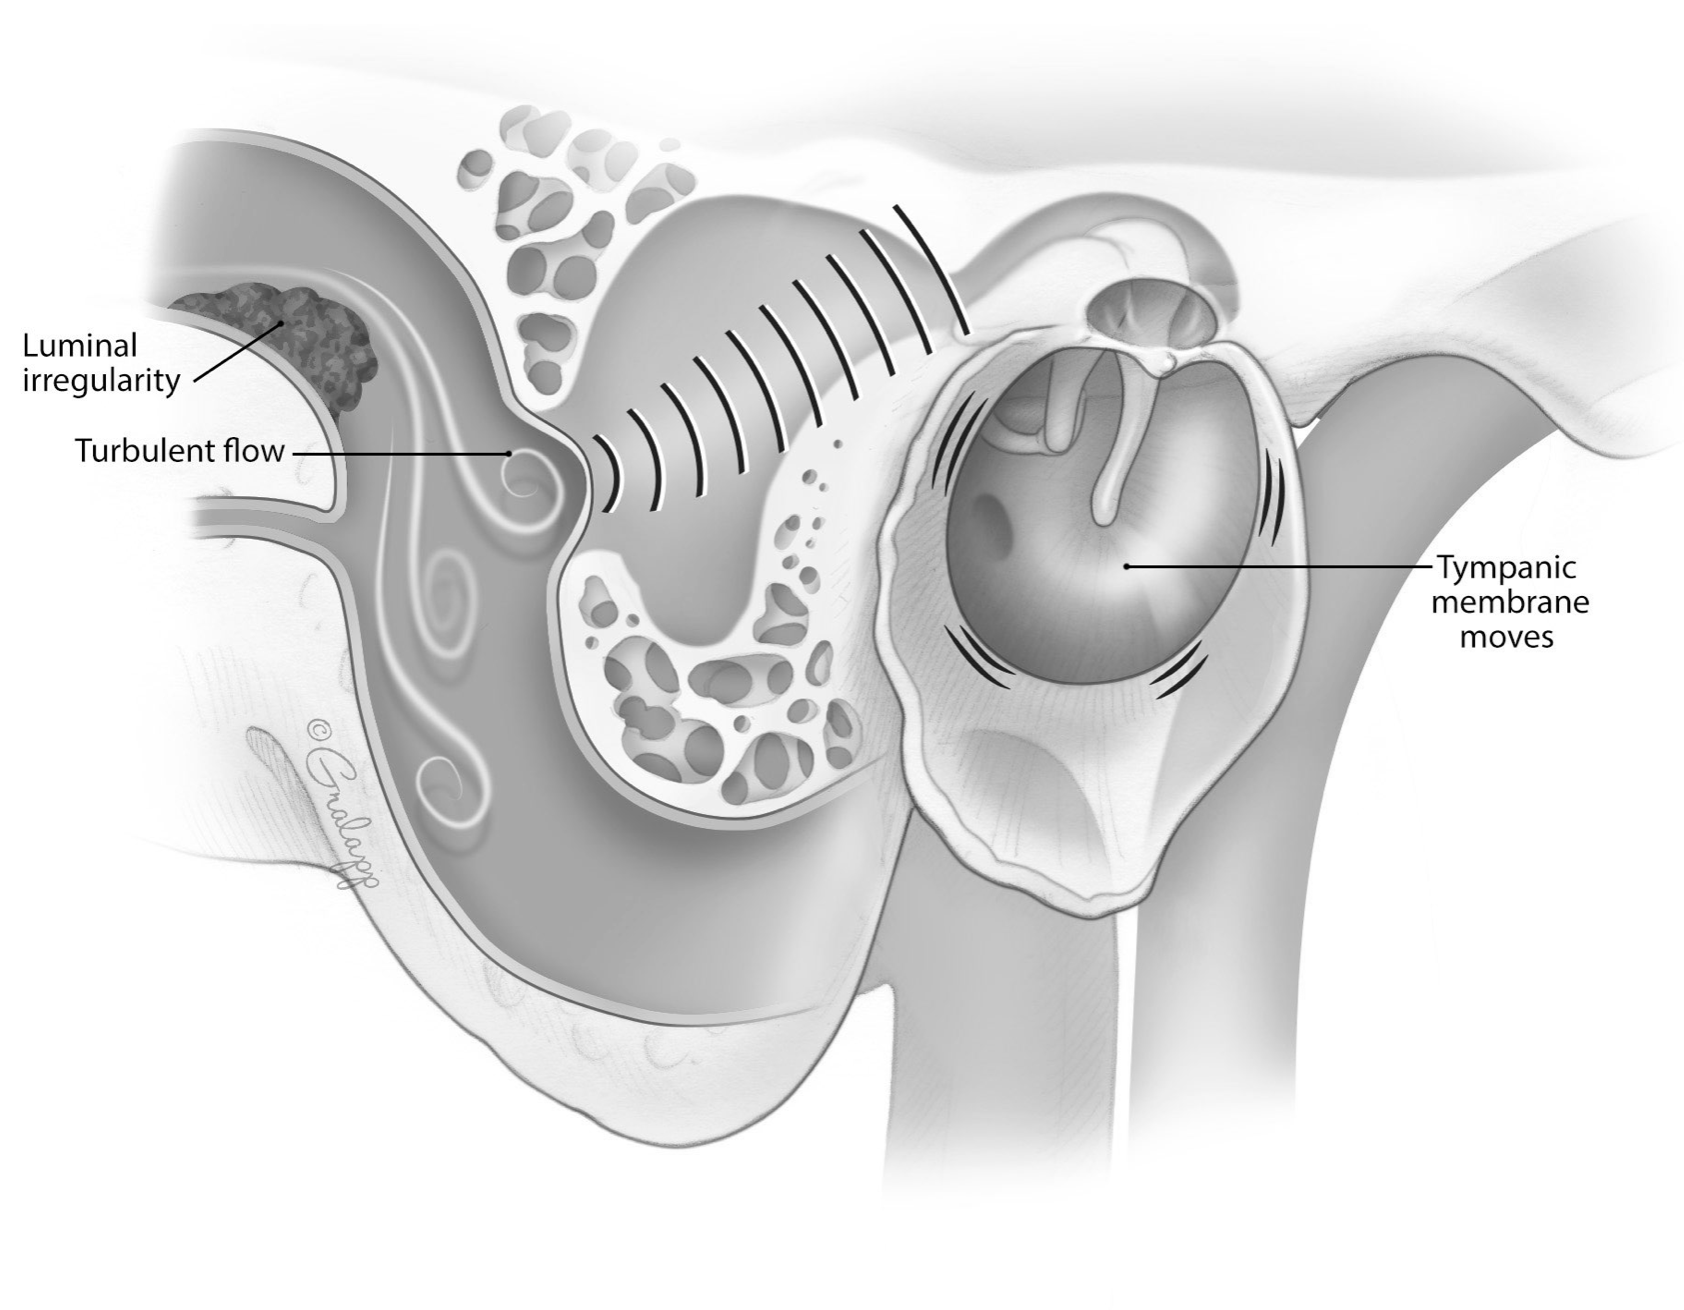

Advanced otology encompasses complex ear and skull base conditions requiring specialized surgical care. We offer cochlear implants and bone conduction implants for hearing loss, treat acoustic neuroma and temporal bone tumors, and perform stapes surgery for otosclerosis. Our team also manages cholesteatoma, superior canal dehiscence, and other advanced ear conditions. Select a topic below to learn more.